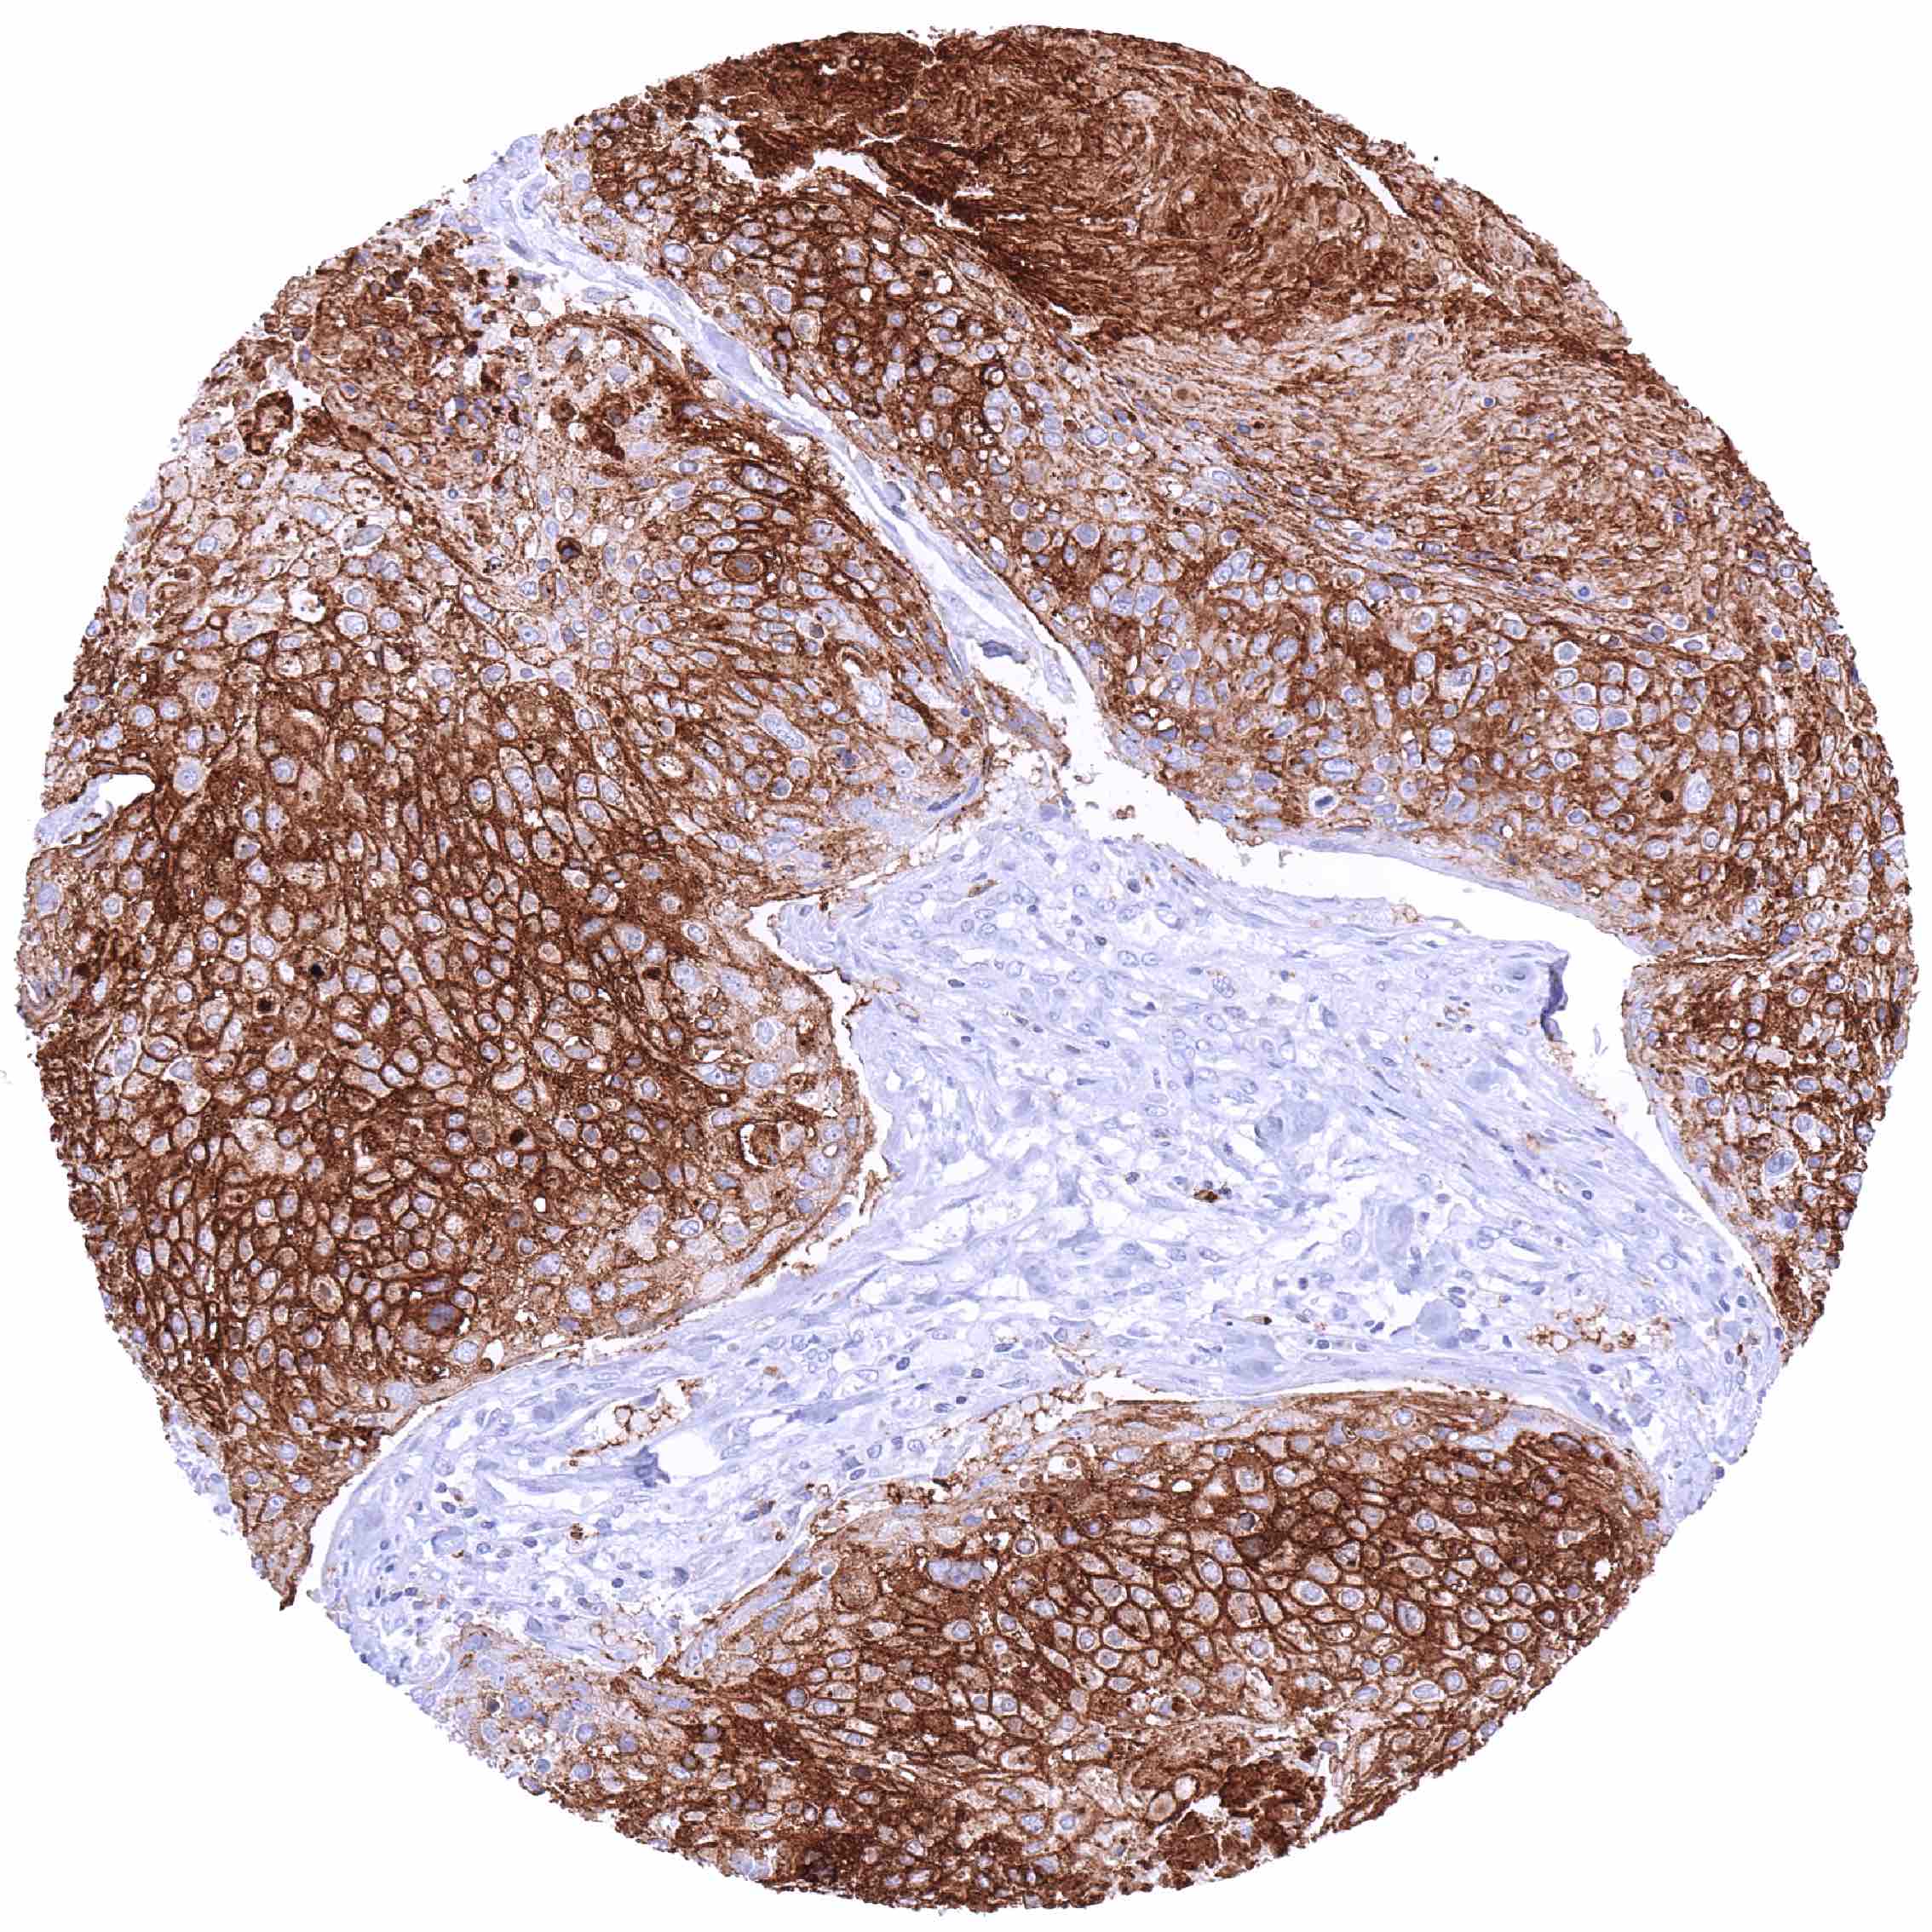

CD70 expression is most commonly seen in different types of lymphoma and in clear cell renal cell carcinoma. Other cancer types have also been described to express CD70 at lower frequency.

Comparison of antibodies: True expression of CD70 in cell types with documented CD70 immunostaining by MSVA-070R is further validated by identical staining patterns obtained by a second, independent CD70 antibody, termed “validation antibody”. The additional membranous staining of heart muscle cells and endothelial cells in many different organs as well as an intense cytoplasmic staining of prostatic epithelial cells which were only seen by using the validation antibody were considered antibody specific cross-reactivities of the validation antibody.